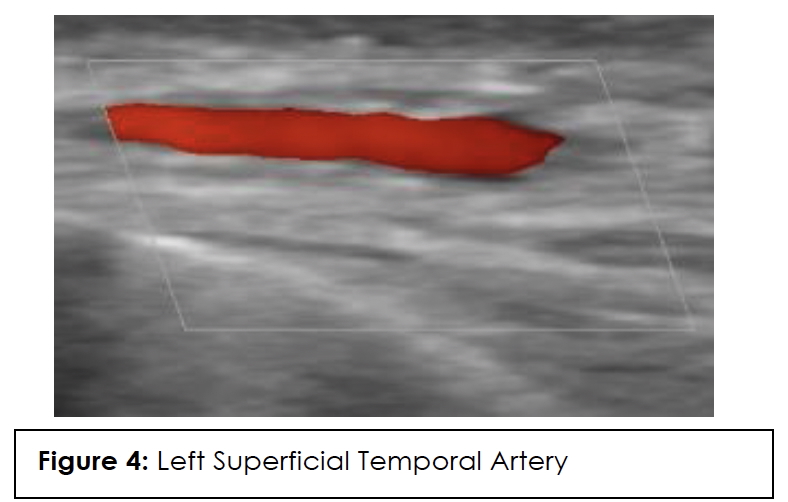

ESR, CRP, and color Doppler ultrasound (CDUS) of his temporal artery in July 2023 were negative, showing no GCA in the superficial temporal arteries. CDUS of bilateral temporal arteries demonstrated normal flow characteristics (Figures 1,2,3,4). Physical examination and temporal predominance of headache prompted obtaining the temporal artery biopsy in August 2023, which revealed healing GCA (Figure 5). The presence of myxoid change in the asymmetrically thickened intima and a residual infiltrate of mostly macrophages at the tunica intima-tunica media interface where the internal elastic lamina was absent allowed distinction of healing arteritis from age-related histopathological change, which may resemble healed giant cell arteritis. 3

In addition to laboratory results, color Doppler ultrasound (CDUS) of the temporal artery is now considered first-line for diagnosis because it has a higher sensitivity than temporal artery biopsy and is of lower cost and less invasive. The hallmark “halo sign,” visible on ultrasound, indicates inflammation of the vessel walls. Bilateral temporal “halo sign” is highly specific for GCA.36 In the 2016 TABUL study37 (a multi-center, prospective study for GCA), ultrasound had sensitivity of 54% and specificity of 81%, while temporal artery biopsy had sensitivity of 39% and specificity of 100%. Temporal artery biopsy remains the gold standard for diagnosis. The lower sensitivity of biopsy is likely due to skip lesions and prior corticosteroid treatment. Unexpectedly, our patient’s ultrasound was negative but biopsy was positive for GCA. Temporal artery abnormalities, including beading (irregular contour), prominence, tenderness, and an absent pulse, are reported to significantly increase the likelihood ratio for a positive temporal artery biopsy (TAB).38 Our patient had prominent temporal arteries on examination, giving him an increased likelihood of positive biopsy.

Ultrasound halo size abnormalities reduced after four or more days of high-dose glucocorticoid treatment. The percentage of positive biopsy results dropped significantly when patients began glucocorticoid treatment within 3 days.39 Our patient had the ultrasound performed approximately 20 days before starting the steroids, so the absence of the halo sign cannot be attributed to the steroids.